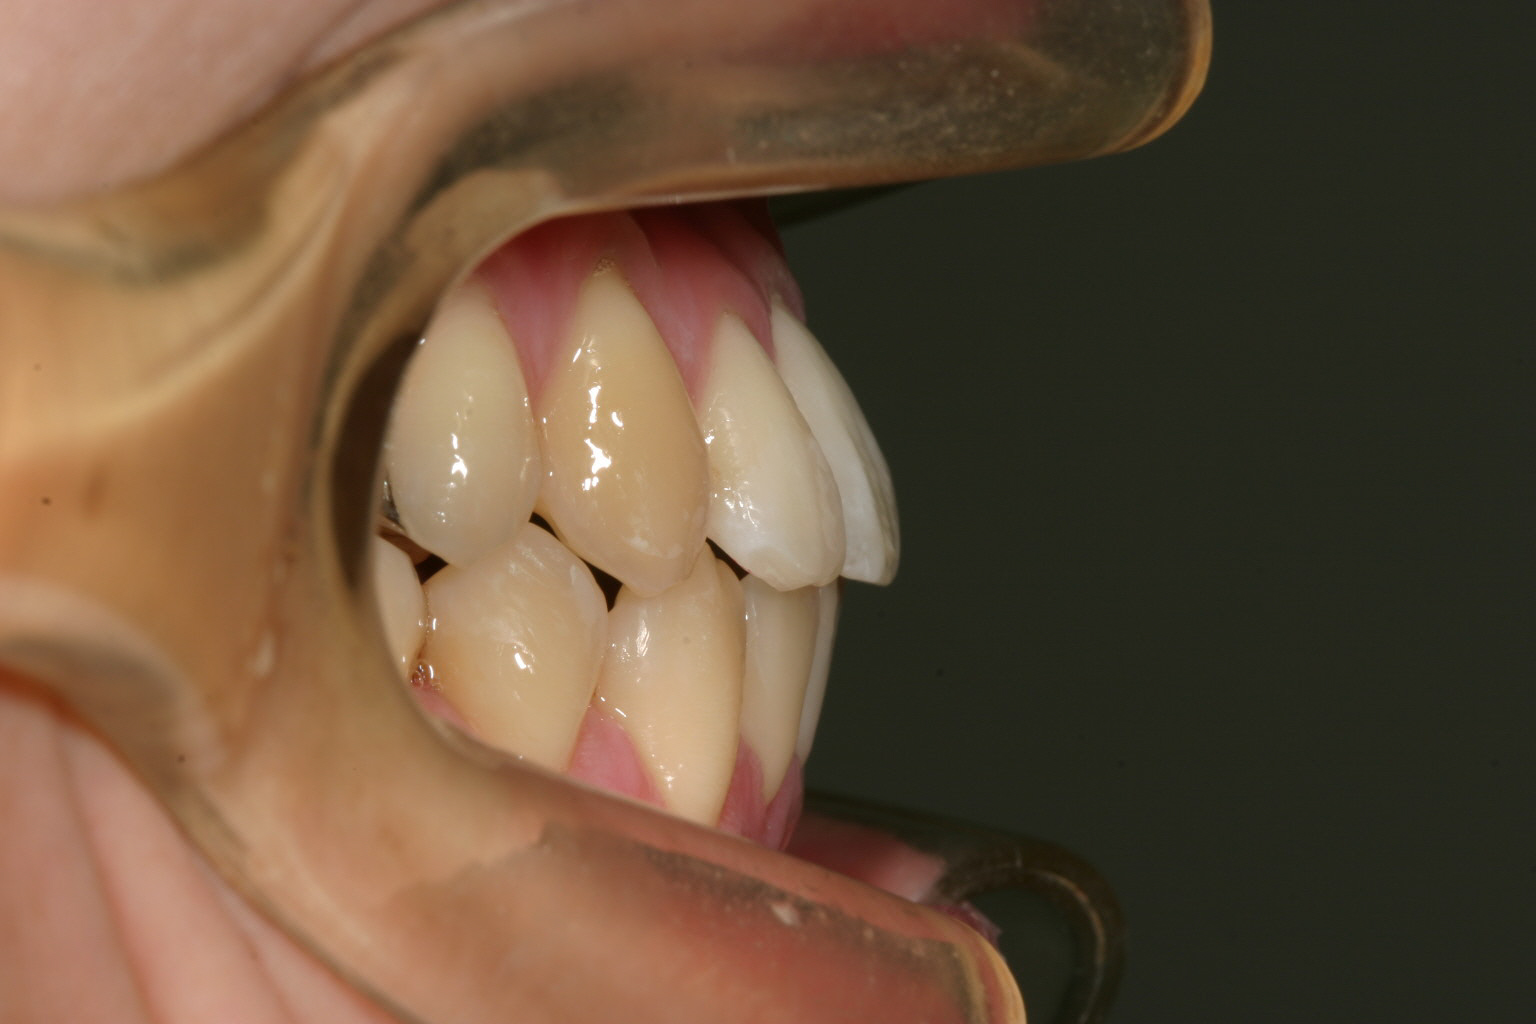

側面観も叢生が目立ちます。

側面観も綺麗ですね~